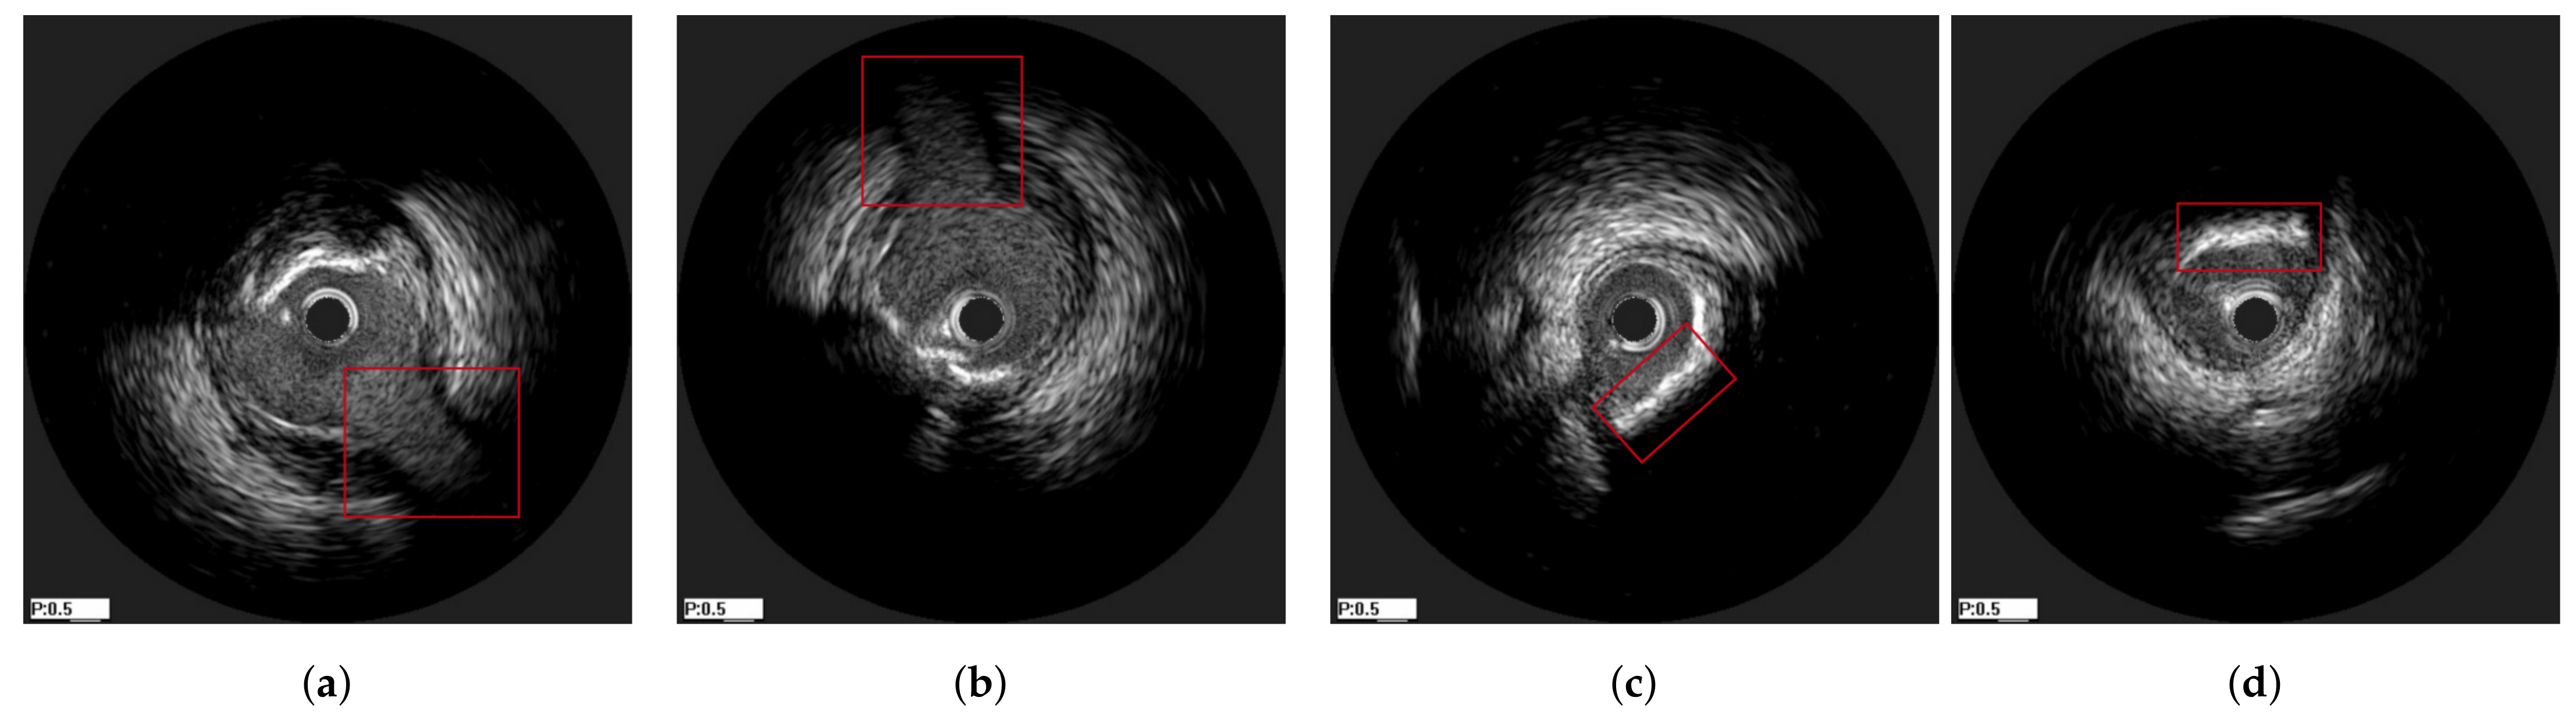

2.1. Data Preparation

3.1. Data Preprocessing